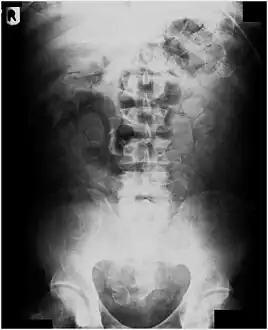

Abdominal X-ray showing small packages of cocaine swallowed by a trafficker.